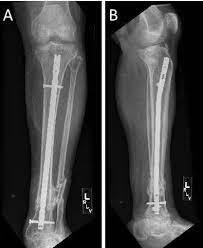

100% fracture union was seen in both cases (Figures 6 and 7). Only one case of deep infection was seen in IMLN group where implant removal and lavage was needed as a secondary procedure. One delayed union in SCP group was managed with removal of 2 screws across fracture site under local anesthesia. Mean time for union was 22 weeks in SCP groups and 19 weeks in IMLN group.

4 cm long incision was made from the inferior pole of patella to the anteromedial aspect of the tibial tuberosity. A patellar tendon splitting approach was used and entry point was visualized. The entry point was made with a diamond awl. Keeping the knee flexed to 90°, with the help of a curved awl, the window was tunneled to the medullary canal. Curved artery forceps was passed over the window created. The guide wire was inserted up to fracture site. Reduction was achieved by traction and closed manipulation of the limb and guide wire passed to the distal fragment. In all the cases sequential reaming was done with flexible reamers passed over the guide wire and minimum 9 mm diameter nail was used. In 2 cases of small diameter canal of the patients 8 mm nail was used. The nail was introduced over guide wire. Further fine reduction under Image Intensifier was achieved and the nail was negotiated into the distal fragment with the gentle taps of the hammer over the nail head. Use of blocking screws was done in 4 cases. Locking was done in static or dynamic mode depending on the fracture pattern. Free hand technique was used for distal locking of the nail under image guidance. Impaction was done, by padded gentle strokes over the heel (Figures 4 and 5).